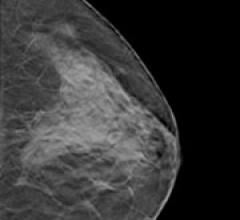

Despite decades of progress in breast imaging, one challenge continues to test even the most skilled radiologists ...

Until recently, consistent assessment of breast composition was hampered by widely differing technical factors and the ...